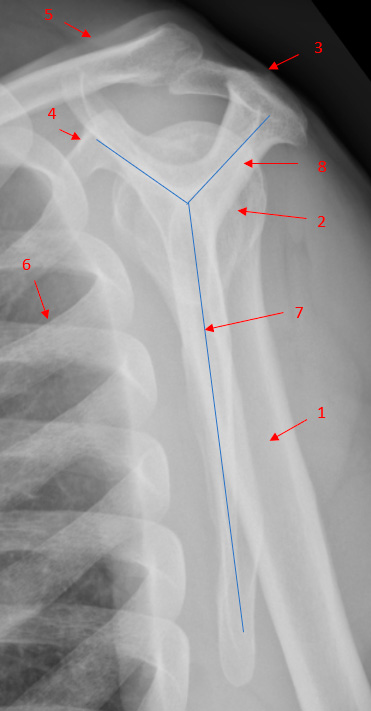

Figur 2:

Normalt lateral billede af skulderleddet (Y-projektion)

Caput humeri skal være centreret over Y´et. Costae ligger foran skulderleddet.

- Humerus (overarmsknoglen)

- Caput humeri (ledhovedet øverst på overarmsknoglen)

- Acromion (Skulderhøjden)

- Processus Coracoideus

- Clavicula (kraveben)

- Costa (ribben)

- Corpus capula (skulderblad)